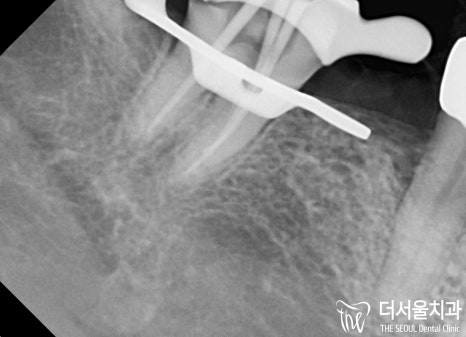

자, 이제 문제가 되었던 과잉치를 살펴봐야겠죠?

발치한 곳은 골소실이 심했기 때문에

다량의 뼈이식을 진행했습니다.

이후 골융합 정도를 살펴보고 나서

네비게이션 임플란트 를 도와드리기로 했죠.